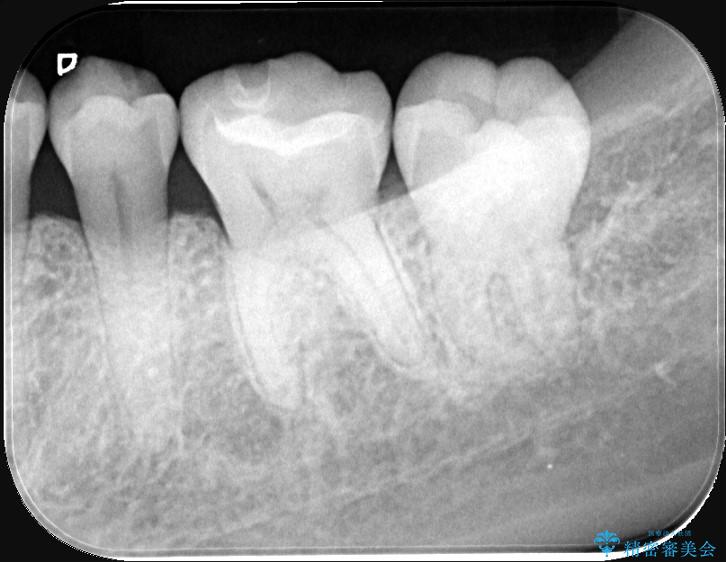

歯が欠けたことによるものか、もしくは以前装着された修復物の不適合が原因と考えられますが、銀歯(メタルインレー)と歯との間に大きな段差が認められ、汚れが溜まりやすい状態となっていました。

このような状態では、修復物の内部で虫歯が進行している可能性が高いため、治療が必要と判断しました。

今回は、経年的な劣化が少なく、汚れが付着しにくいセラミックインレーを用いて治療を行いました。